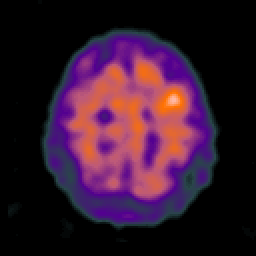

Alzheimer's disease: overlay -- Slice #20

[Home][Help][Clinical] Slice 20